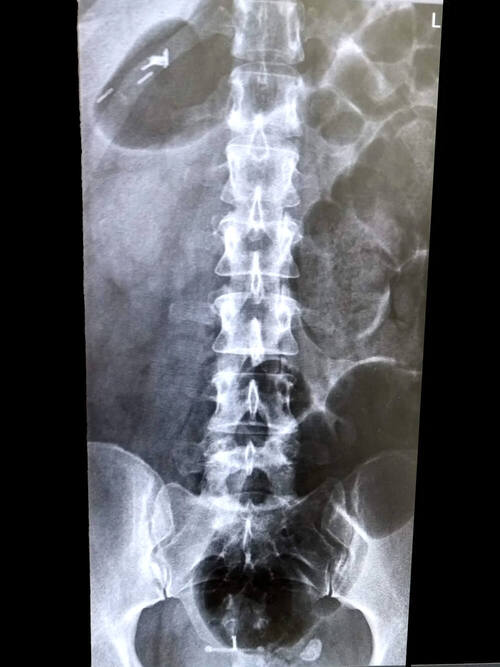

Fracturas Vertebrales

Las fracturas vertebrales son muy frecuentes a nivel mundial y se originan por la fragilidad ósea, generalmente son consecuencia de la osteoporosis.